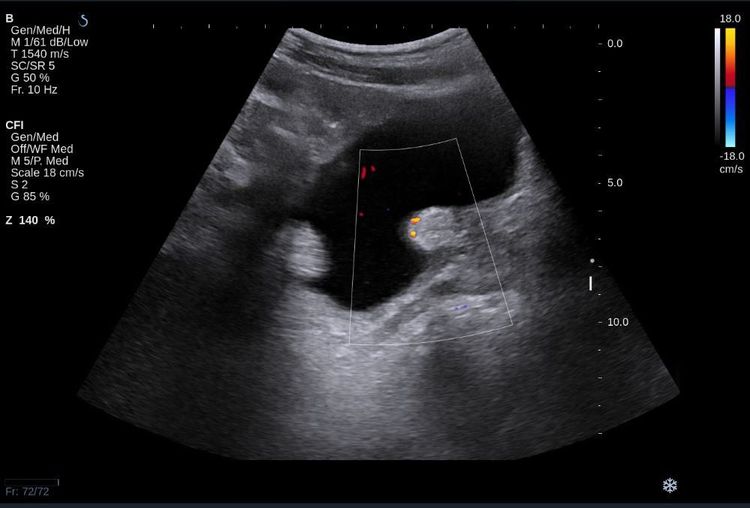

Siêu âm là một xét nghiệm tiện lợi, nhanh chóng, hiệu quả chính xác cao giúp bác sỹ có thể thấy được hình ảnh của toàn bộ lòng bàng quang và thành bàng quang, từ đó có thể nhìn thấy được 1 hoặc nhiều u, đôi khi thấy được cả hình ảnh thâm nhiễm của u.

Siêu âm cũng là phương tiện theo dõi tái phát sau điều trị nội soi u nông bàng quang. Ngoài ra còn thấy được hình ảnh thận, bể thận, tiền liệt tuyến,…

4. Hình ảnh u bàng quang trên siêu âm

Bệnh lý bàng quang có nhiều dấu hiệu khác nhau, từ đó hình ảnh siêu âm cũng khác nhau. Các bệnh lý bàng quang thường gặp:

Ung thư biểu mô tế bào chuyển tiếp Lồi dưới dạng polyp